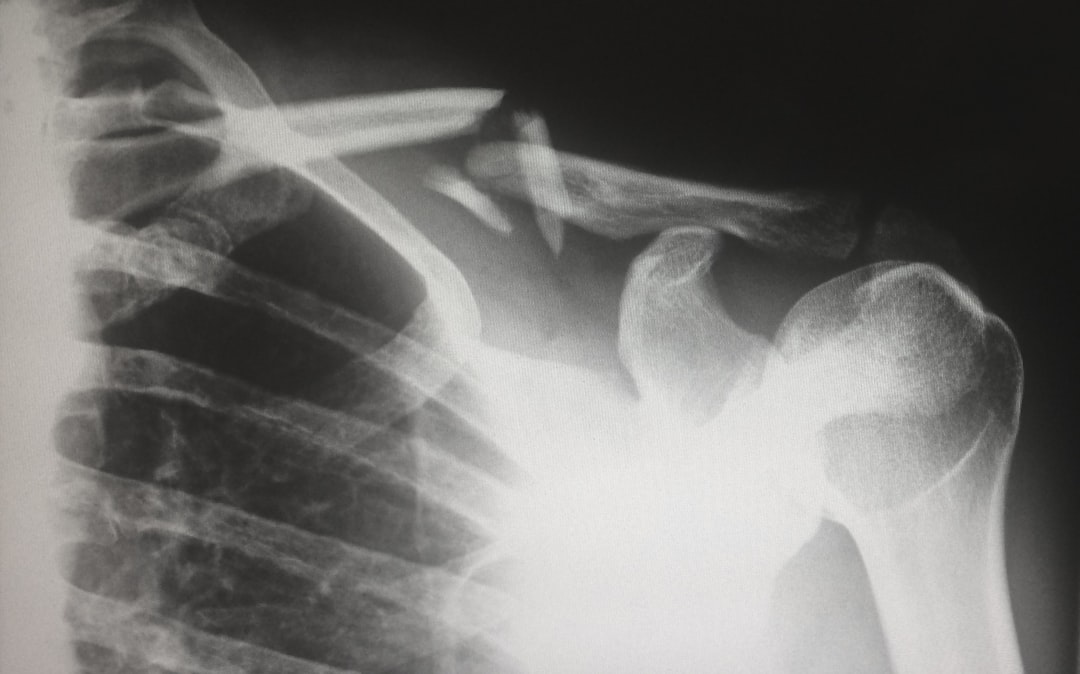

Az alsó végtagi érszűkület műtét egy orvosi beavatkozás, amelyet a lábak vérellátásának javítása érdekében végeznek. Az érszűkület, más néven perifériás artériás betegség (PAD), akkor alakul ki, amikor az artériák falán lerakódások, például koleszterin és kalcium...